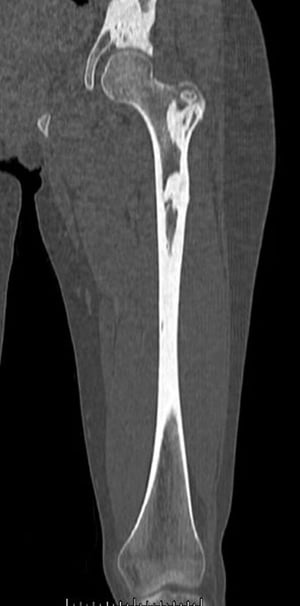

このCT画像には,大腿骨および骨盤に生じたメロレオストーシスの密度の高い骨病変が認められる。

Image courtesy of Michael J. Joyce, MD, and David M.Joyce, MD.